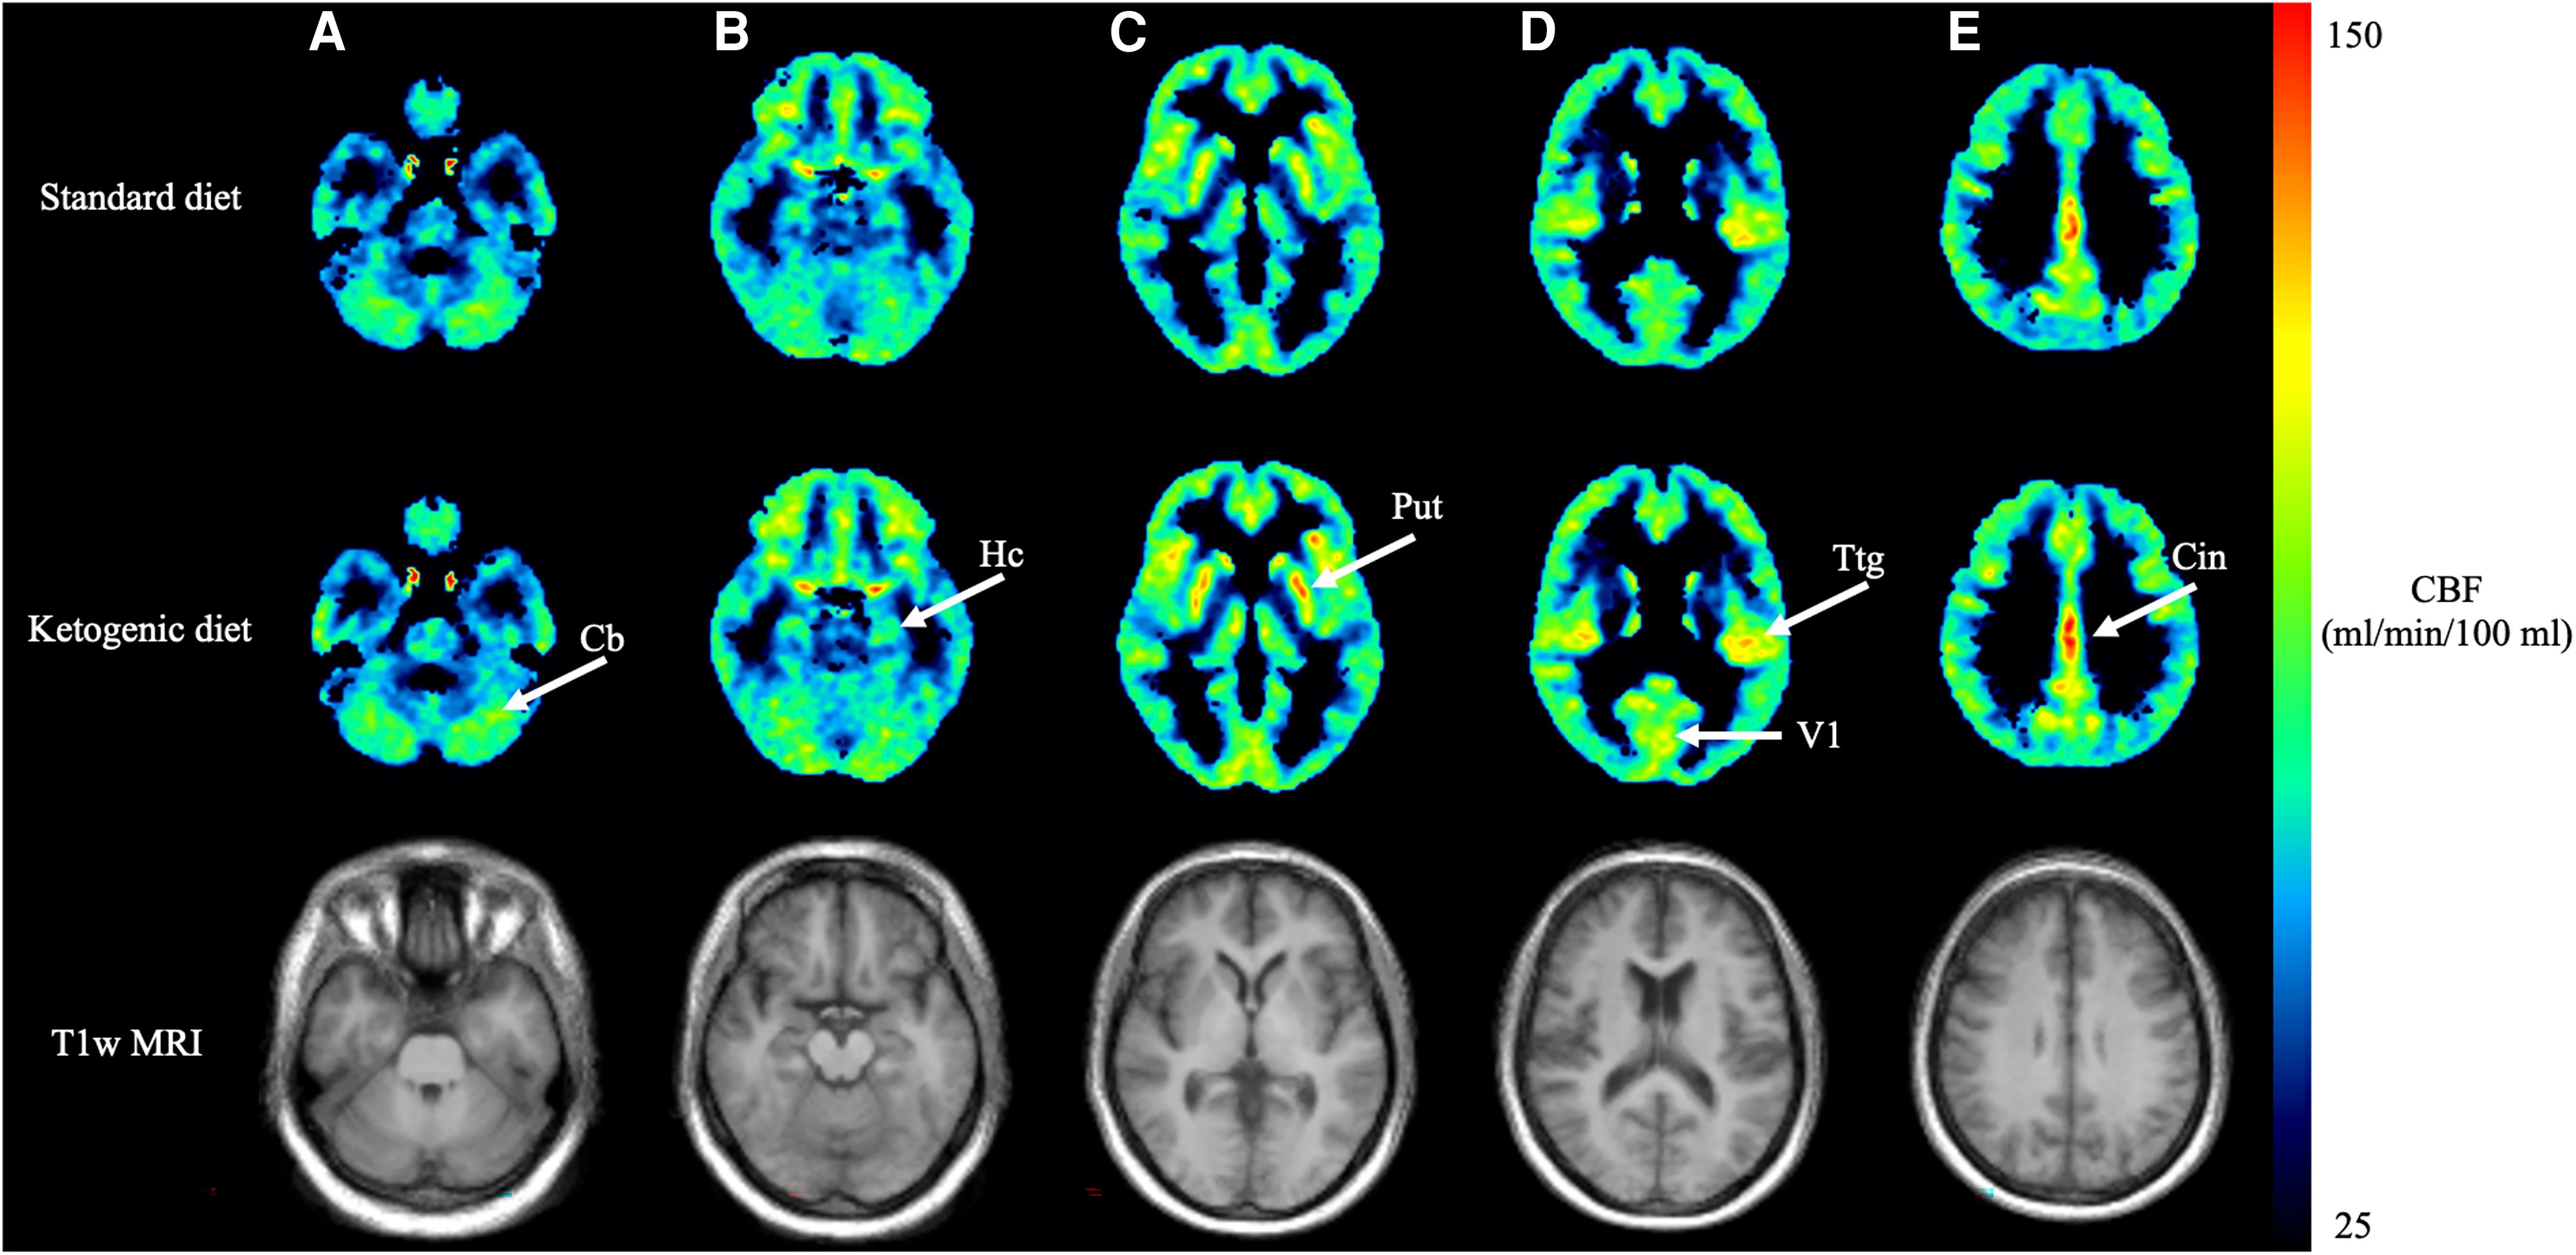

Researchers examined 11 healthy adults (none of whom had neurological conditions or other health problems), exploring how their brains responded to two distinct diets: a low-carb, high-fat ketogenic diet (5% carbohydrates, 20% protein, and 75% fat) versus a more traditional diet rich in carbohydrates (45–60% carbs, 10–20% protein, and 25–40% fat). Each participant followed these diets for three weeks, undergoing detailed brain imaging scans and blood tests before and after each phase.

Following the ketogenic diet, participants experienced an impressive 47% rise in levels of brain-derived neurotrophic factor (BDNF)—a crucial protein that supports brain health, neuron growth, and cognitive function. Even more remarkable was the observed 22% increase in cerebral blood flow.

The most notable improvements occurred in three critical brain areas: the cerebellum—essential for coordination, fine-tuning movements, and motor learning (think of smoothly riding a bike) and also influential in attention and language; the hippocampus—central to memory formation, spatial navigation (remembering where you parked your car or left your keys), and the conversion of short-term memories into lasting ones; and the cingulate gyrus—vital for emotional regulation, decision-making, error detection, and empathy, shaping the integration of emotions and cognition.

Interestingly, the boost in cerebral blood flow was tightly correlated with higher blood ketones, suggesting ketones directly enhance blood delivery to the brain.